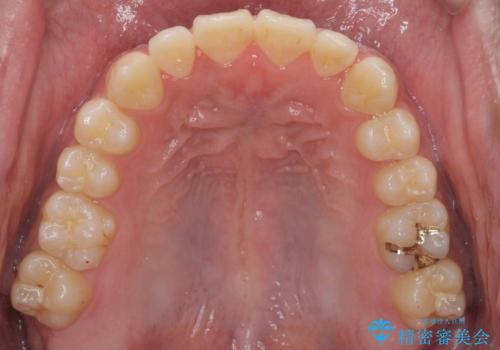

骨格性の受け口 非抜歯で下の歯を後ろに下げる インビザラインで インプラント矯正

- 受け口を主訴に来院。

他院でマウスピース矯正を始めたが、担当医に不信感をもち転院。

当院では下の歯を後ろに下げるため矯正用ミニスクリューを用いてしっかり移動を行う等ご説明をし、治療開始しました。